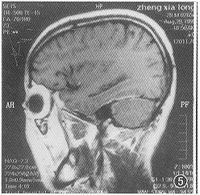

图5 1999年8月(确诊治疗15个月后)MRI矢状位增强扫描示右颞叶水肿消失,沟、回重现,侧脑室颞角恢复正常

出院7个月后,1998年4月,出现精神异常,时而安静,时而烦躁打骂亲人,曾送精神病院治疗未见好转。1998年5月13日来院复查。除精神症状外,一般情况良好。MRI颅脑横断面、冠状及矢状位扫描并增强显示:右中颅窝底硬脑膜、右侧小脑幕均见明显强化的带状影,右侧颞叶水肿,局部脑沟消失(图2);右侧脑室颞角受压变小(图3);右侧海绵窦影明显增大,增厚的窦壁使颈内动脉受压变细(图4)。根据MRI所见及临床症状确诊为弥漫性肥厚性硬脑膜炎伴右颞叶水肿及器质性精神障碍。每天青霉素静脉点滴10 000 000 U共26 d,临床症状消失。1999年8月28日(15个月后)复查 MRI,颞叶水肿消退,沟回重现,侧脑室颞角恢复正常(图5),肥厚的硬脑膜因已纤维化,故不再强化,但右侧颈内动脉仍受压(图6),2000年4月(23个月后)电话询问,患者工作、生活良好,并已成婚。